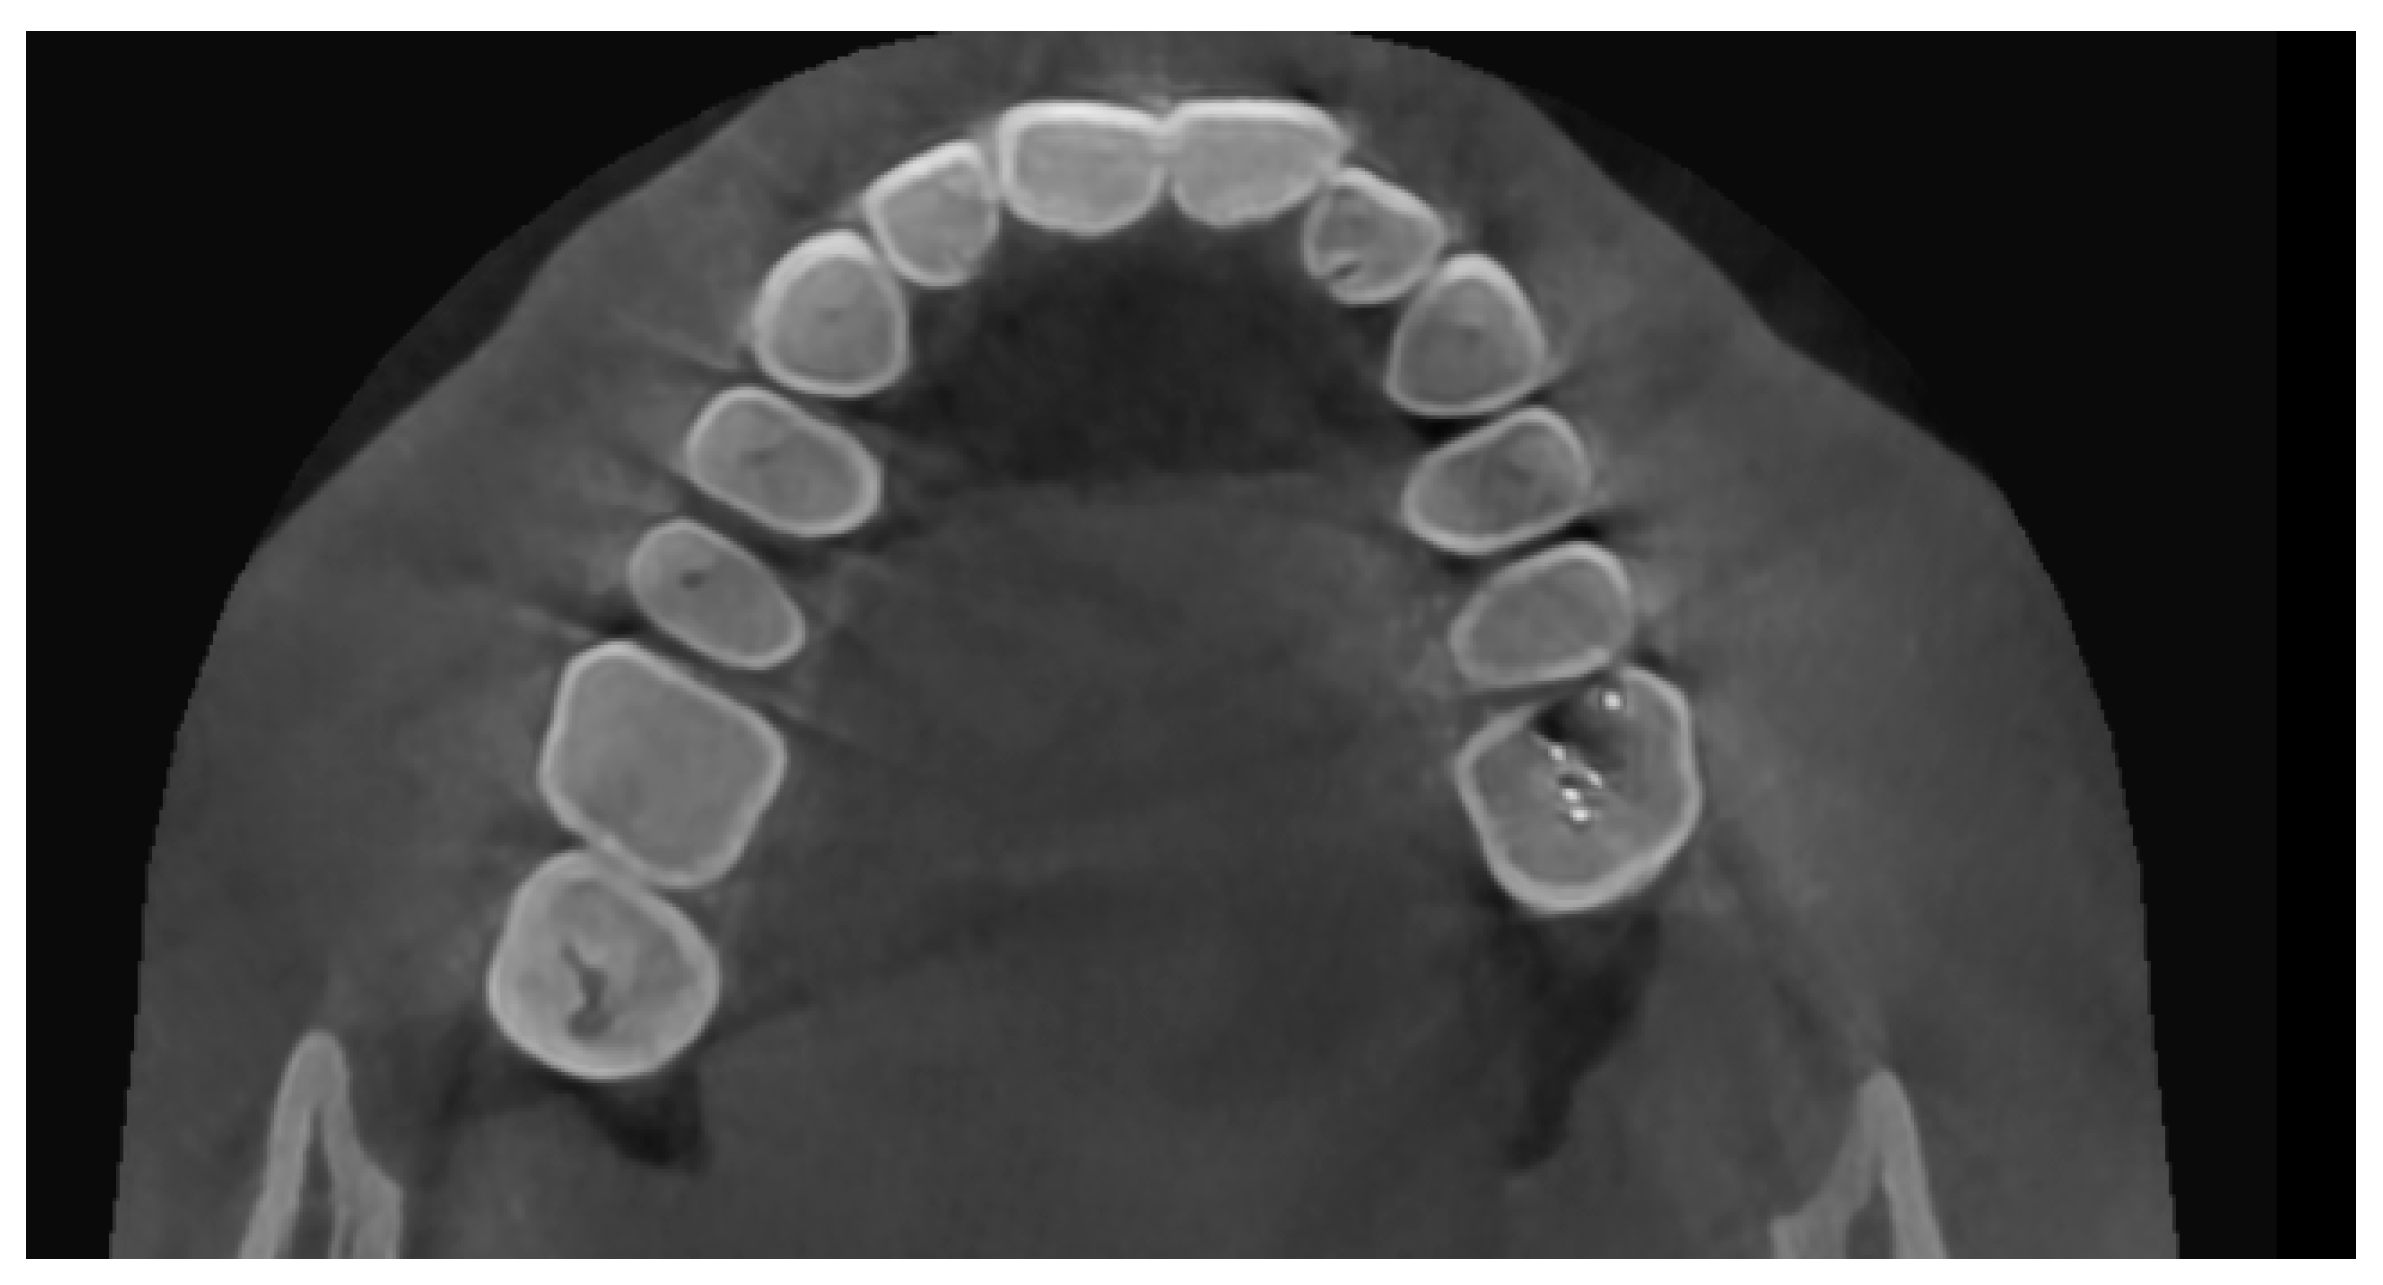

On CBCT, there were beam hardening streaking artifacts (black lines) present in the volume (Figure 1). Upon assessing the axial section at the root end–maxillary sinus floor interface, the streaking artifact had mimicked the destruction of the sinus floor and communication between the sinus and periapical pathology (Figure 2), indicating a radiodiagnosis of odontogenic sinusitis. Upon a surgical exploration with root end surgery, this was proven to be a periapical scar and an intact maxillary sinus floor.

Figure 1. Beam hardening streaking artifacts (black lines) in the axial section.

Figure 2. At the root end–maxillary sinus floor interface, the streaking artifact mimicked the destruction of the sinus floor and communication between the sinus and periapical pathology.